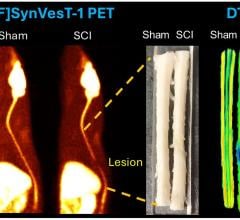

Sept. 11, 2025 — A new PET tracer can provide insights into how spinal cord injuries affect not only the spinal cord ...